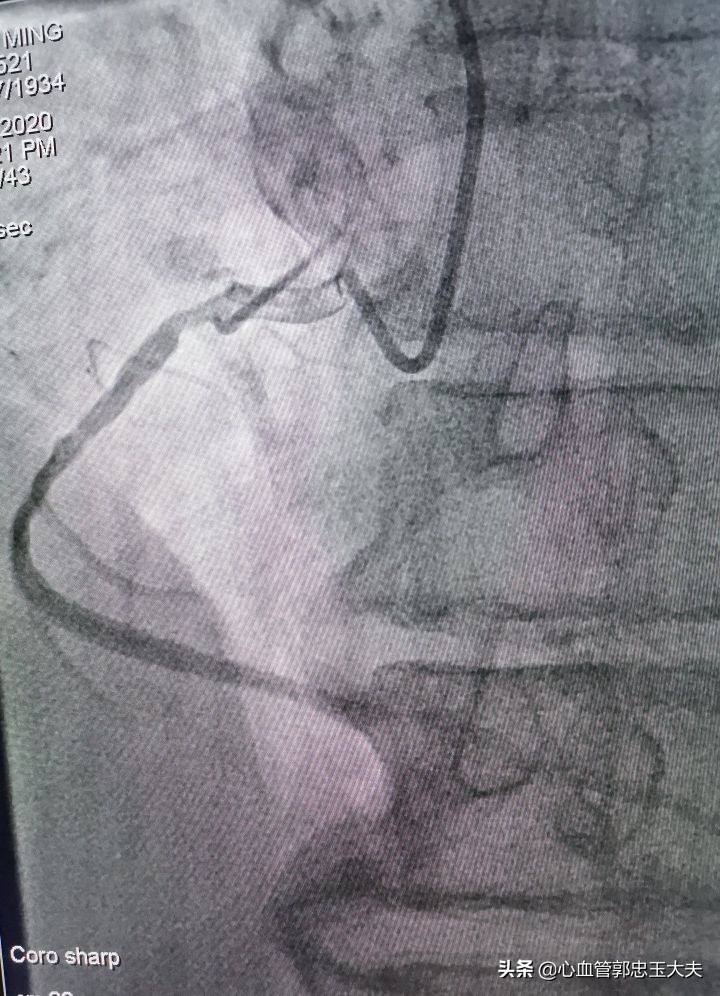

右冠近中段50~75%狭窄(如下图)